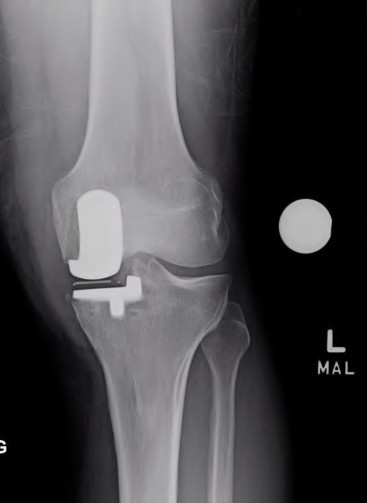

A 65-year-old man presents with anterior knee pain and a feeling of instability during stair climbing 1 year after a primary total knee arthroplasty.

Examination reveals a lateral patellar tilt. CT scan is performed to evaluate component rotation. Which of the following errors in component positioning is most likely responsible for his symptoms?

Explanation

Internal rotation of the femoral component or the tibial component increases the Q angle, leading to lateral patellar maltracking, lateral patellar tilt, and anterior knee pain. External rotation of the components generally improves patellar tracking.